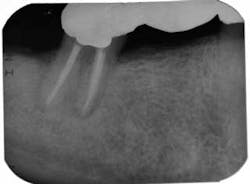

Endodontic case study: Healing of a large lesion in a lower molar after proper dental instrumentation and irrigation

On the second appointment, the calcium hydroxide was rinsed out and the canals reinstrumented. QMix was again placed into the canals and agitated with EndoActivator. The canals were filled using warm vertical condensation with System B and Calamus backfill. The patient was given a six-month follow-up appointment and ibuprofen 600 mg for postoperative discomfort. I again stressed to the patient that the prognosis for this tooth was guarded. At the six-month follow-up appointment, the patient had been asymptomatic and there was clear evidence of healing.